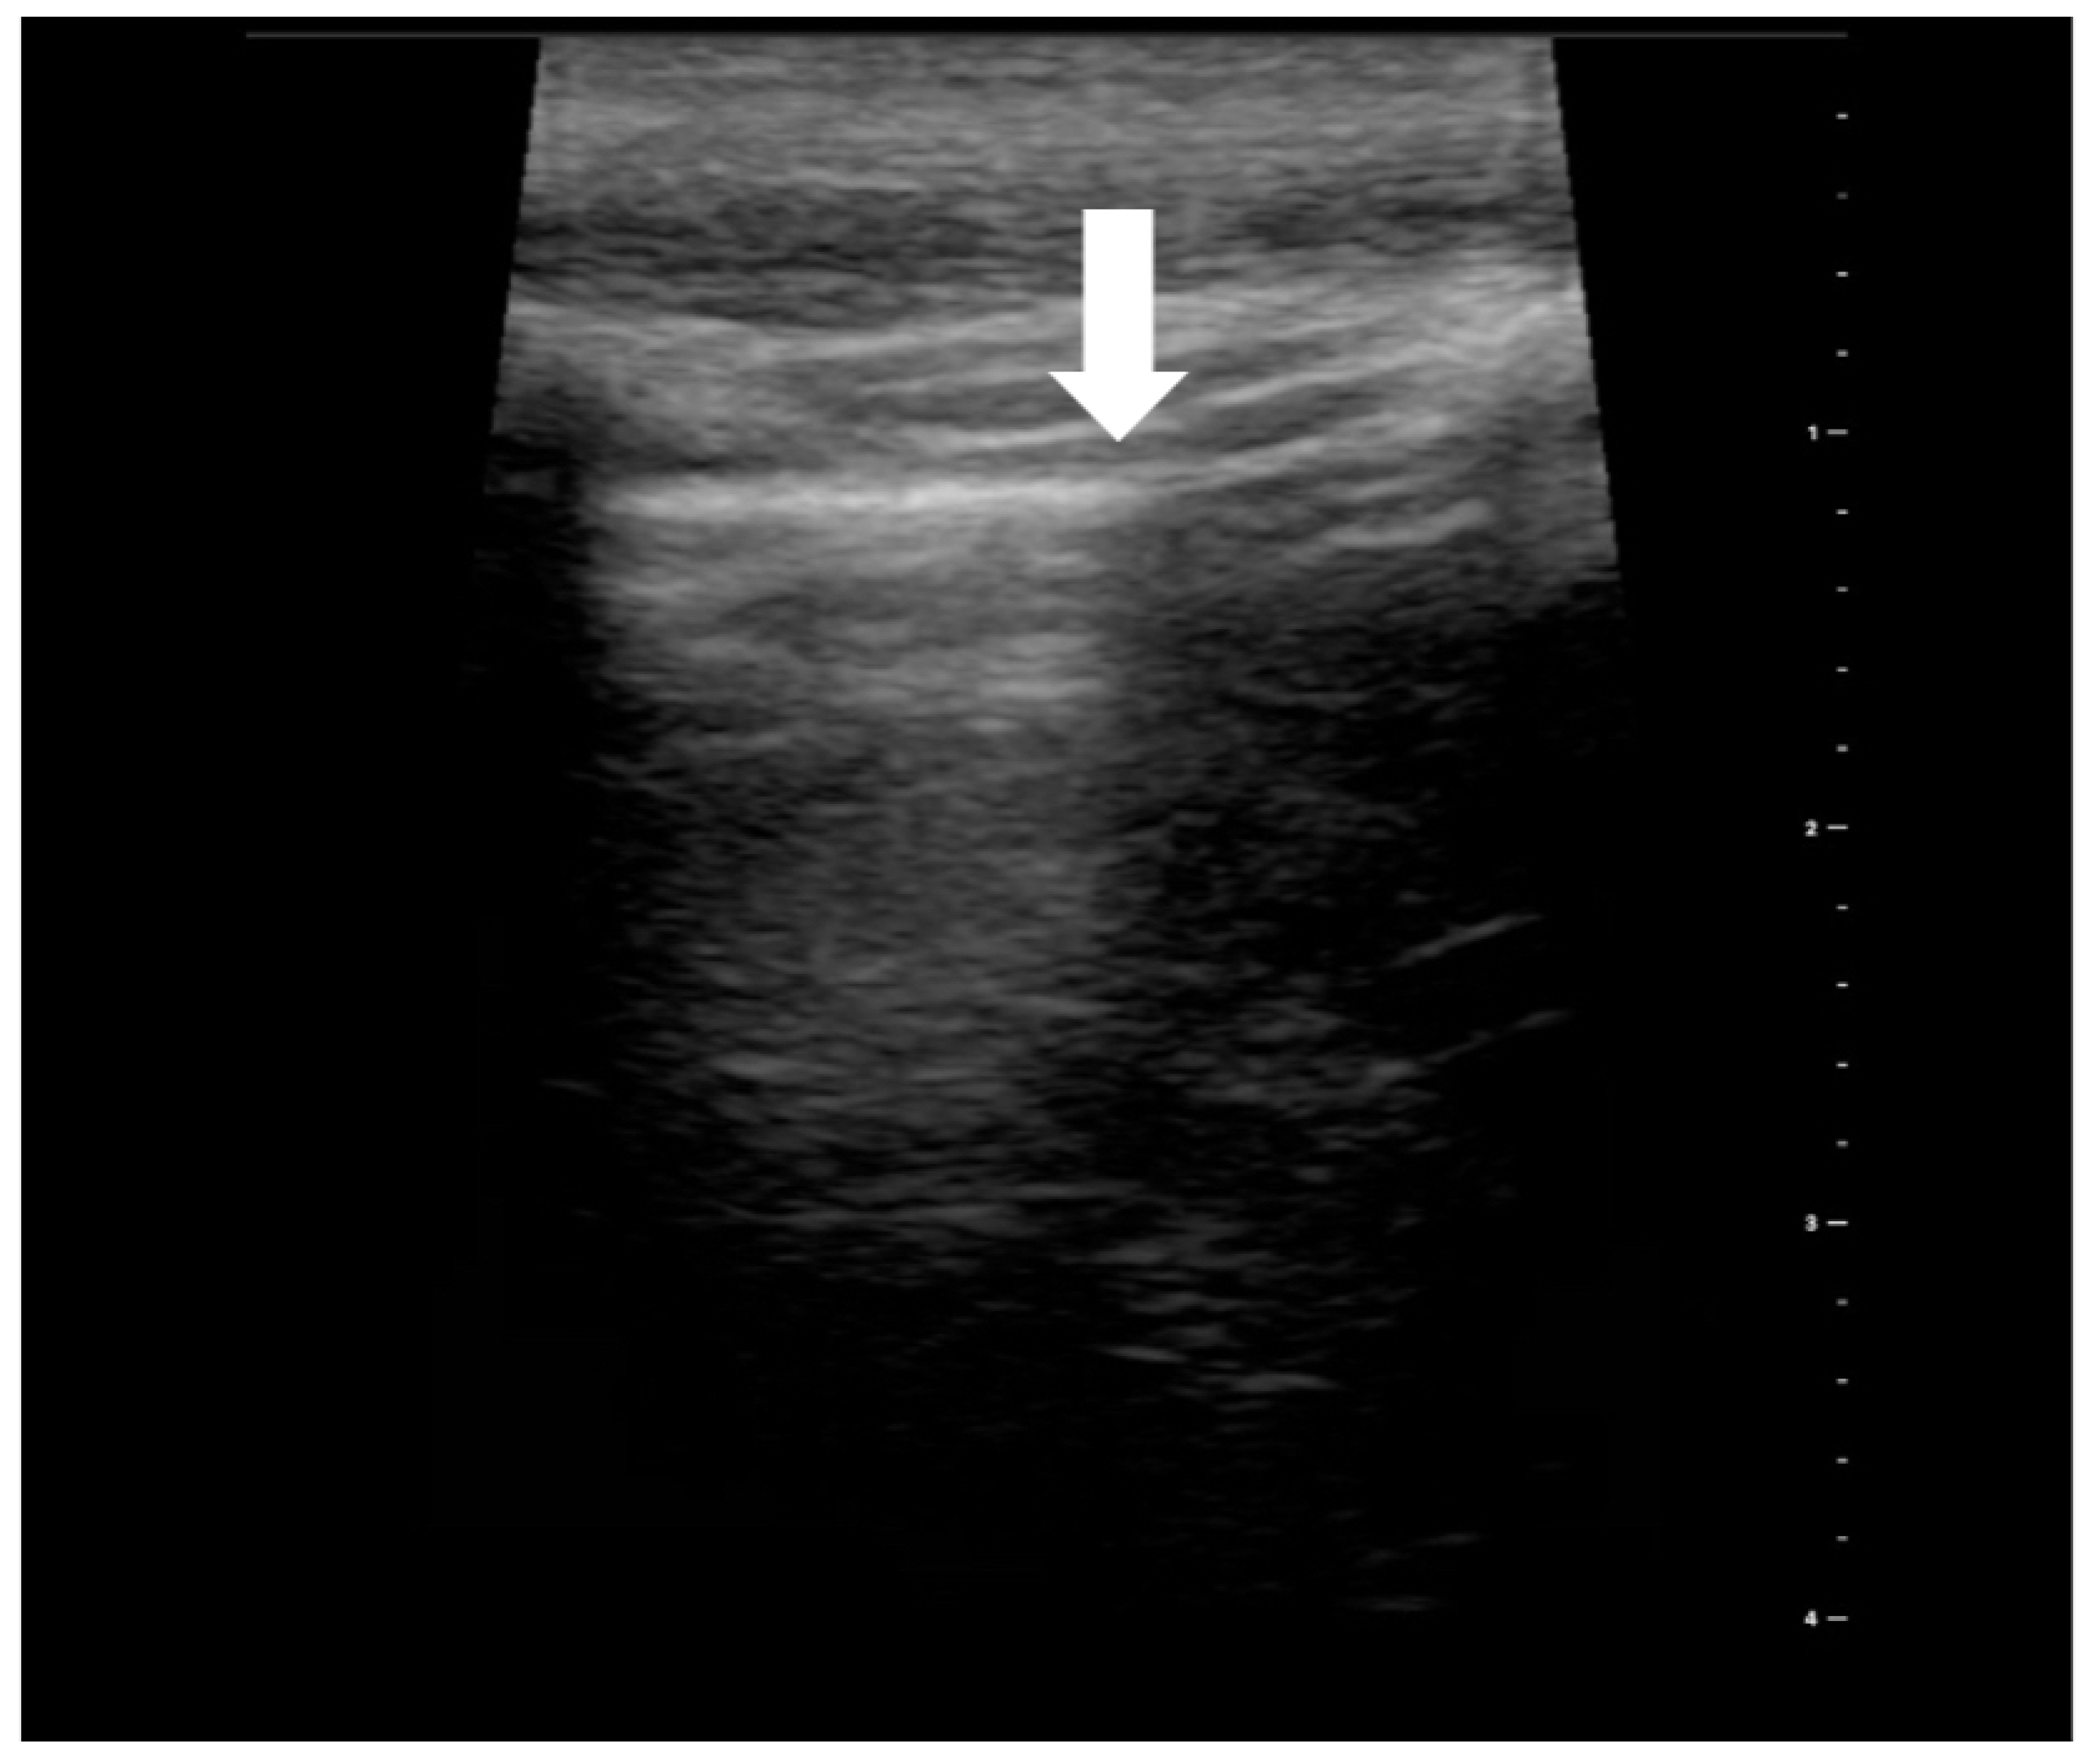

5. BLUE Protocol

To quickly identify and treat the cause of acute respiratory failure, in 2008, Lichtenstein introduced the BLUE (bedside lung ultrasound in emergency) protocol [18]. To date, it is the best known and most accurate of the existing LUS protocols. This study aimed to target diagnostic imaging to identify life-threatening conditions that can lead to acute respiratory failure. Lichtenstein’s task was to develop a protocol by which an ultrasound technician could perform a bedside ultrasound examination in a matter of minutes and implement the correct treatment based on six ultrasound probe positions. The examination is carried out in the chest’s upper (Figure 3), lateral, and posterolateral areas (Figure 4). Within the described six regions on both sides of the chest, the presence of characteristic ultrasound images and signs are assessed, among which are: the A (Figure 5) and B lines (Figure 6), lung sliding sign, lung point (Figure 7), tissue-like sign, and shred sign [18].

Figure 6. Ultrasound symptom “B-lines” (source: author’s material-DK).